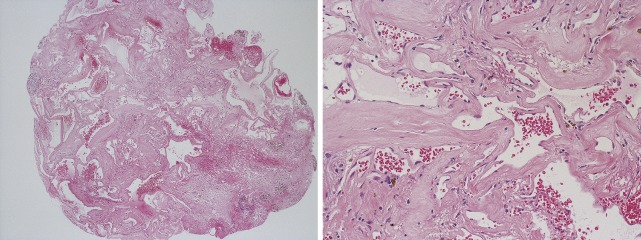

图2,在较低(左)和较高(右)放大倍数下切除病灶的苏木精-伊红染色。内皮细胞扁平的扩张薄壁血管突出。